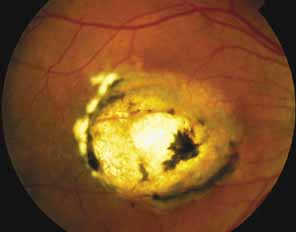

Best's vitelliform macular dystrophy (VMD2; MIM No. 153700) is an autosomal macular dystrophy that usually presents early in life with dome-shaped yellowish macular lesions that eventually partially resorb, develop scarring, or are replaced by choroidal atrophy, which, if extensive, can simulate choroidal sclerosis (Fig. 18).6,115–117 The ERG in Best's macular dystrophy is normal, but the EOG shows a diagnostic pattern of subnormal, slow oscillations and normal, fast oscillations of the resting potential.8 The gene for Best's disease has been linked to chromosome 11q13.118 The gene, VMD2, has been discovered119 and its product, bestrophin, appears to be a member of a new family of chloride channels that is important for generation of the light rise of the electrooculogram.120,121

Fig. 18 Left eye of a 78-year-old woman with Best's vitelliform macular dystrophy, showing central choroidal atrophy with loss of retinal pigment epithelium and choriocapillaris, similar to what has been called central choroidal sclerosis. The visual acuity was 20/400. This woman is individual II-2 in the pedigree reported by Stone et al.118 that demonstrated linkage of Best's disease with markers on chromosome 11q13. (From Stone EM: Heritable disorders of RPE, Bruch's membrane, and the choriocapillaris. In Wright K, Ellis F, Mets M, et al [eds]: Pediatric Ophthalmology. Philadelphia: JB Lippincott, 1995)